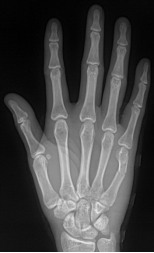

手骨

包括腕骨、掌骨、指 骨

腕骨共8块,近侧由桡侧向尺侧为:手舟骨、月骨、三角骨和

豆骨,远侧列为:大多角骨、小多角骨、头状骨和钩骨

8块腕骨构成一掌面凹陷的腕骨沟

掌骨共5块,近端为底,接腕骨;远端为头,接指骨;中间部为体

指骨共14块,拇指有2节,分为近节和远节指骨,其余各指为3节, 分为近节指骨,中节指骨和远节指骨。每节指骨近端为底,中间部为体,远端为滑车